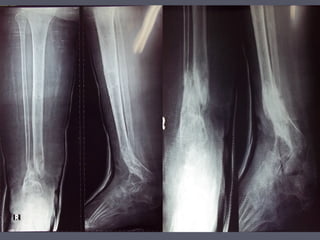

Case1 varus deformityCase1 varus deformity

Case 2 calcaneus deformityCase 2 calcaneus deformity

Case 3 equinus deformityCase 3 equinus deformity